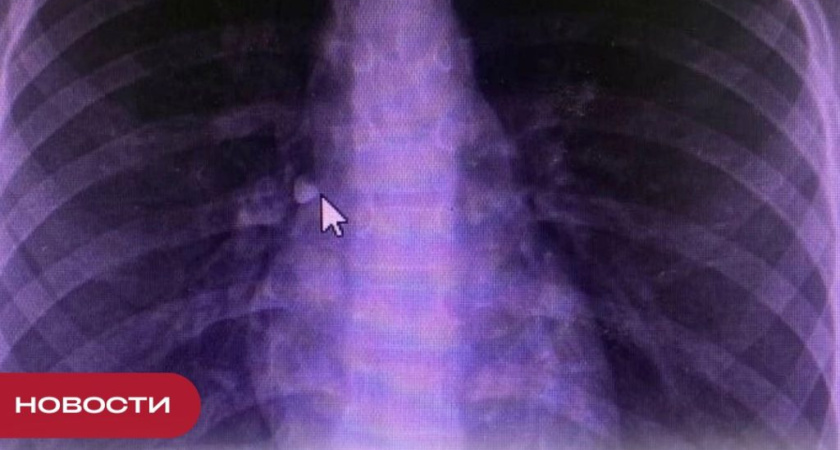

У девочки сразу начались проблемы с дыханием, она экстренно поступила в Республиканскую детскую клиническую больницу. «Девочка экстренно поступила в хирургическое отделение с проблемами с дыханием. Врачи провели рентгенографическое исследование и бронхоскопию и обнаружили инородный предмет в бронхе. В таких случаях извлечь посторонний предмет можно эндоскопическим способом, что и было сделано – врач-эндоскопист Евгений Абрамов извлек зуб из правого главного бронха. Через несколько дней ребенок был выписан в удовлетворительном состоянии», – рассказал главный врач РДКБ Павел Пупков. Инородные предметы в дыхательных путях и желудочно-кишечном тракте часто становятся причиной экстренной госпитализации детей. Ежегодно в РДКБ извлекаются до 20 инородных предметов – чаще всего это монеты, батарейки, иголки, магниты, маленькие игрушки или конфеты. Если ребенок кашляет, задыхается, плачет, тяжело дышит, не может говорить – необходимо срочно вызвать бригаду скорой помощи.